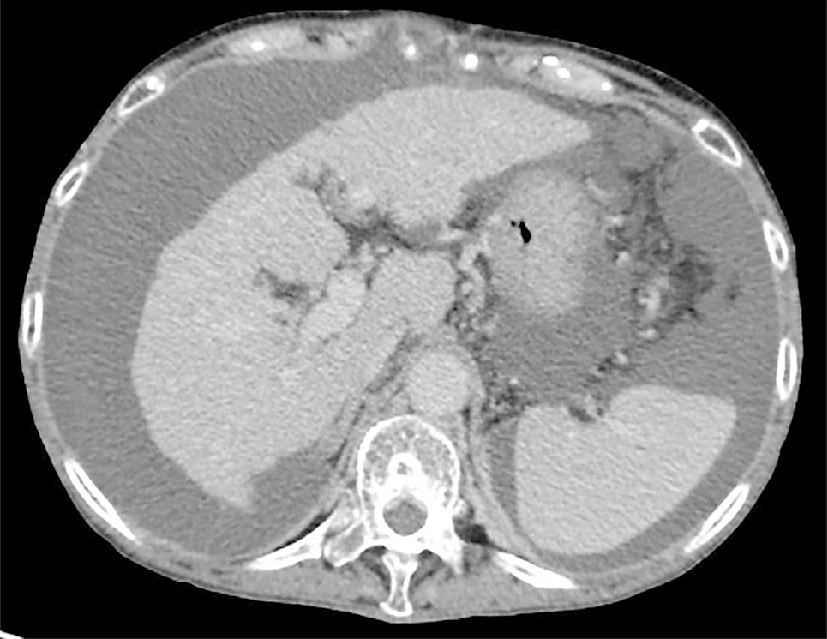

腹水は肝硬変の一般的な合併症です。これは門脈圧亢進症の影響によって起こり、腹部に体液が蓄積します。腹水は、薬、処置、食事の変更によって治療できます。

腹水は肝硬変の最も一般的な合併症です。門脈圧亢進症の影響により腹部に体液が蓄積することが関係します。